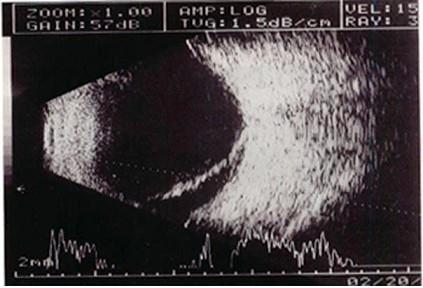

问题 患者眼前闪光,视力减退1周。结合超声声像图,最可能的诊断是?(?)

选项 A.局限性脉络膜脱离  B.局限性视网膜脱离 C.完全性视网膜脱离 D.玻璃体后脱离 E.以上均不对

答案 B